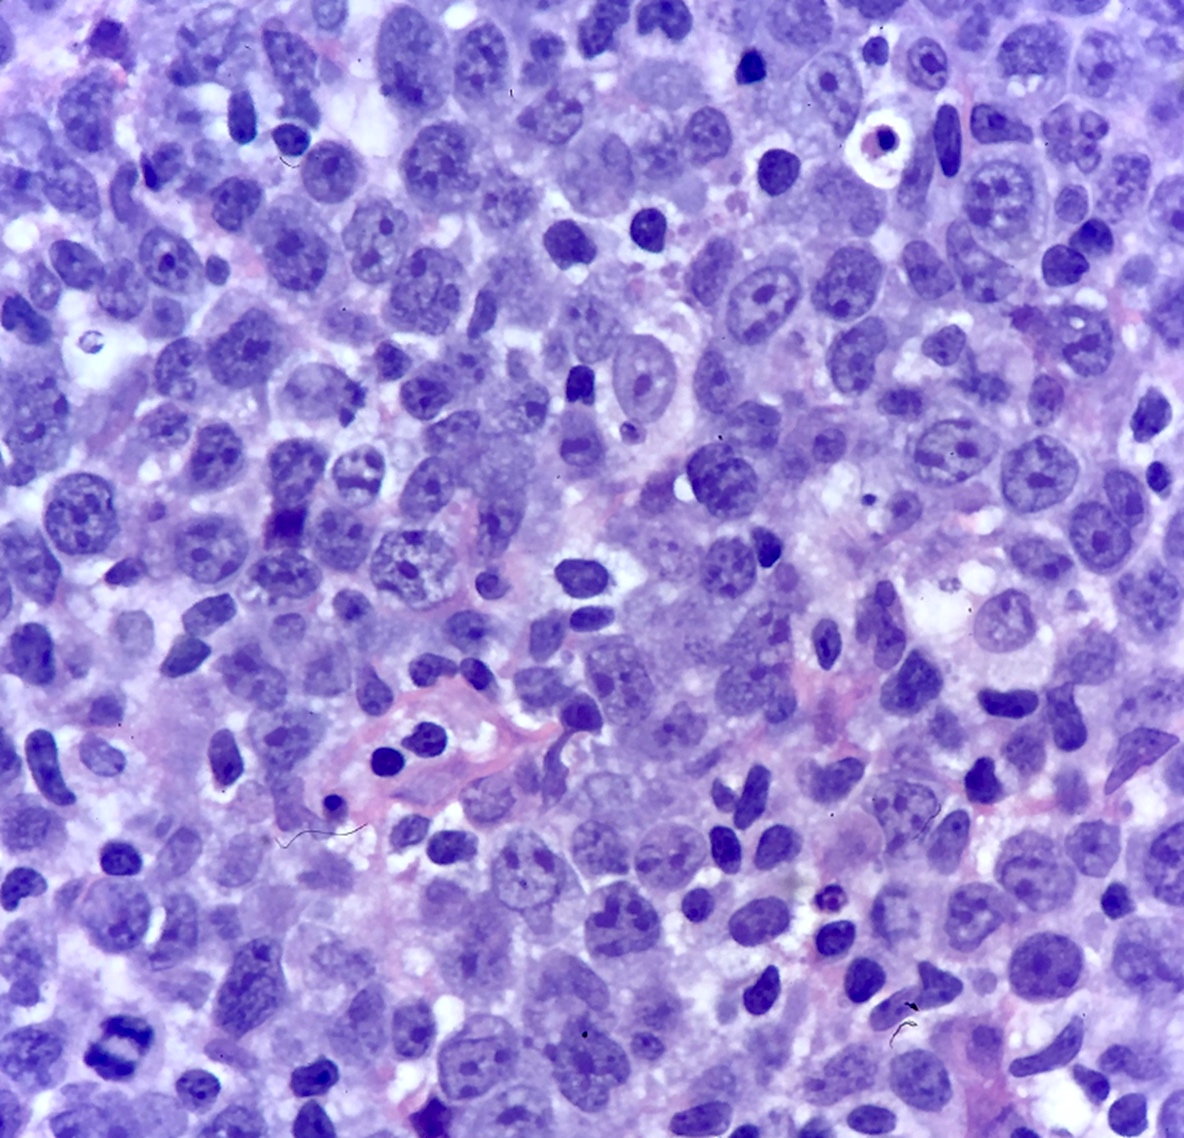

Microscopic (histologic) description

- Partial or complete effacement of normal tissue architecture by a diffuse infiltrate of large (or occasionally medium size) atypical B lymphoid cells with vesicular chromatin and prominent nucleoli

- Large is defined as nucleus size ≥ histiocyte nucleus or > 2 lymphocyte nuclei

- Morphologic variants:

- Immunoblastic variant: single central nucleolus

- Centroblastic variant: 2 - 4 nucleoli

- Anaplastic variant: anaplastic nuclei, can mimic anaplastic large cell lymphoma or Reed-Sternberg cells

Microscopic (histologic) images